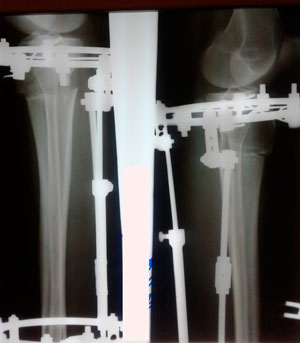

на фиксации

IMG_7170-18-11-19-07-54.JPG

IMG_7169-18-11-19-07-54.JPG